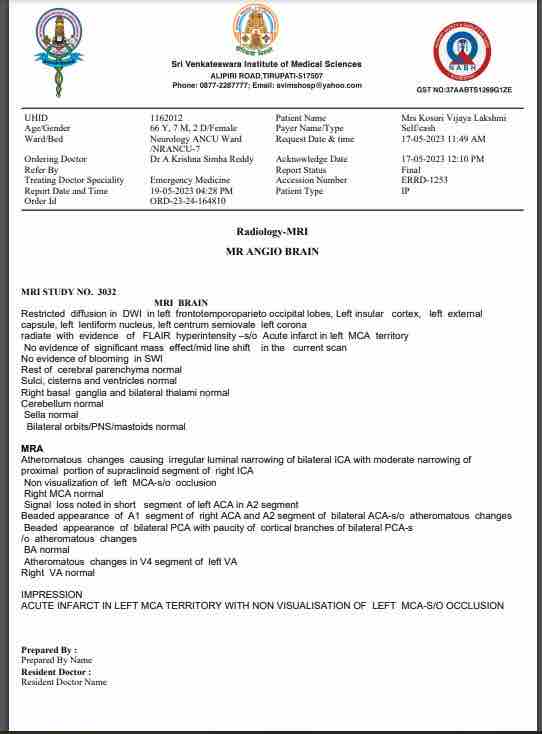

We are reaching out to you today with a heavy heart and a plea for help. Our beloved 66-year-old mother K VIJYA LAKSHMI, has been facing an incredibly challenging journey since 16th May when she had brain stroke & underwent emergency brain and abdomen surgery. Her recovery has been a rollercoaster of ups and downs.

During her hospitalization, she endured multiple complications, including respiratory distress, recurrent severe infections, and even seizure-like activity. Through it all, she has shown immense strength and determination. Still she require three more surgeries to stand on the path of recovery.